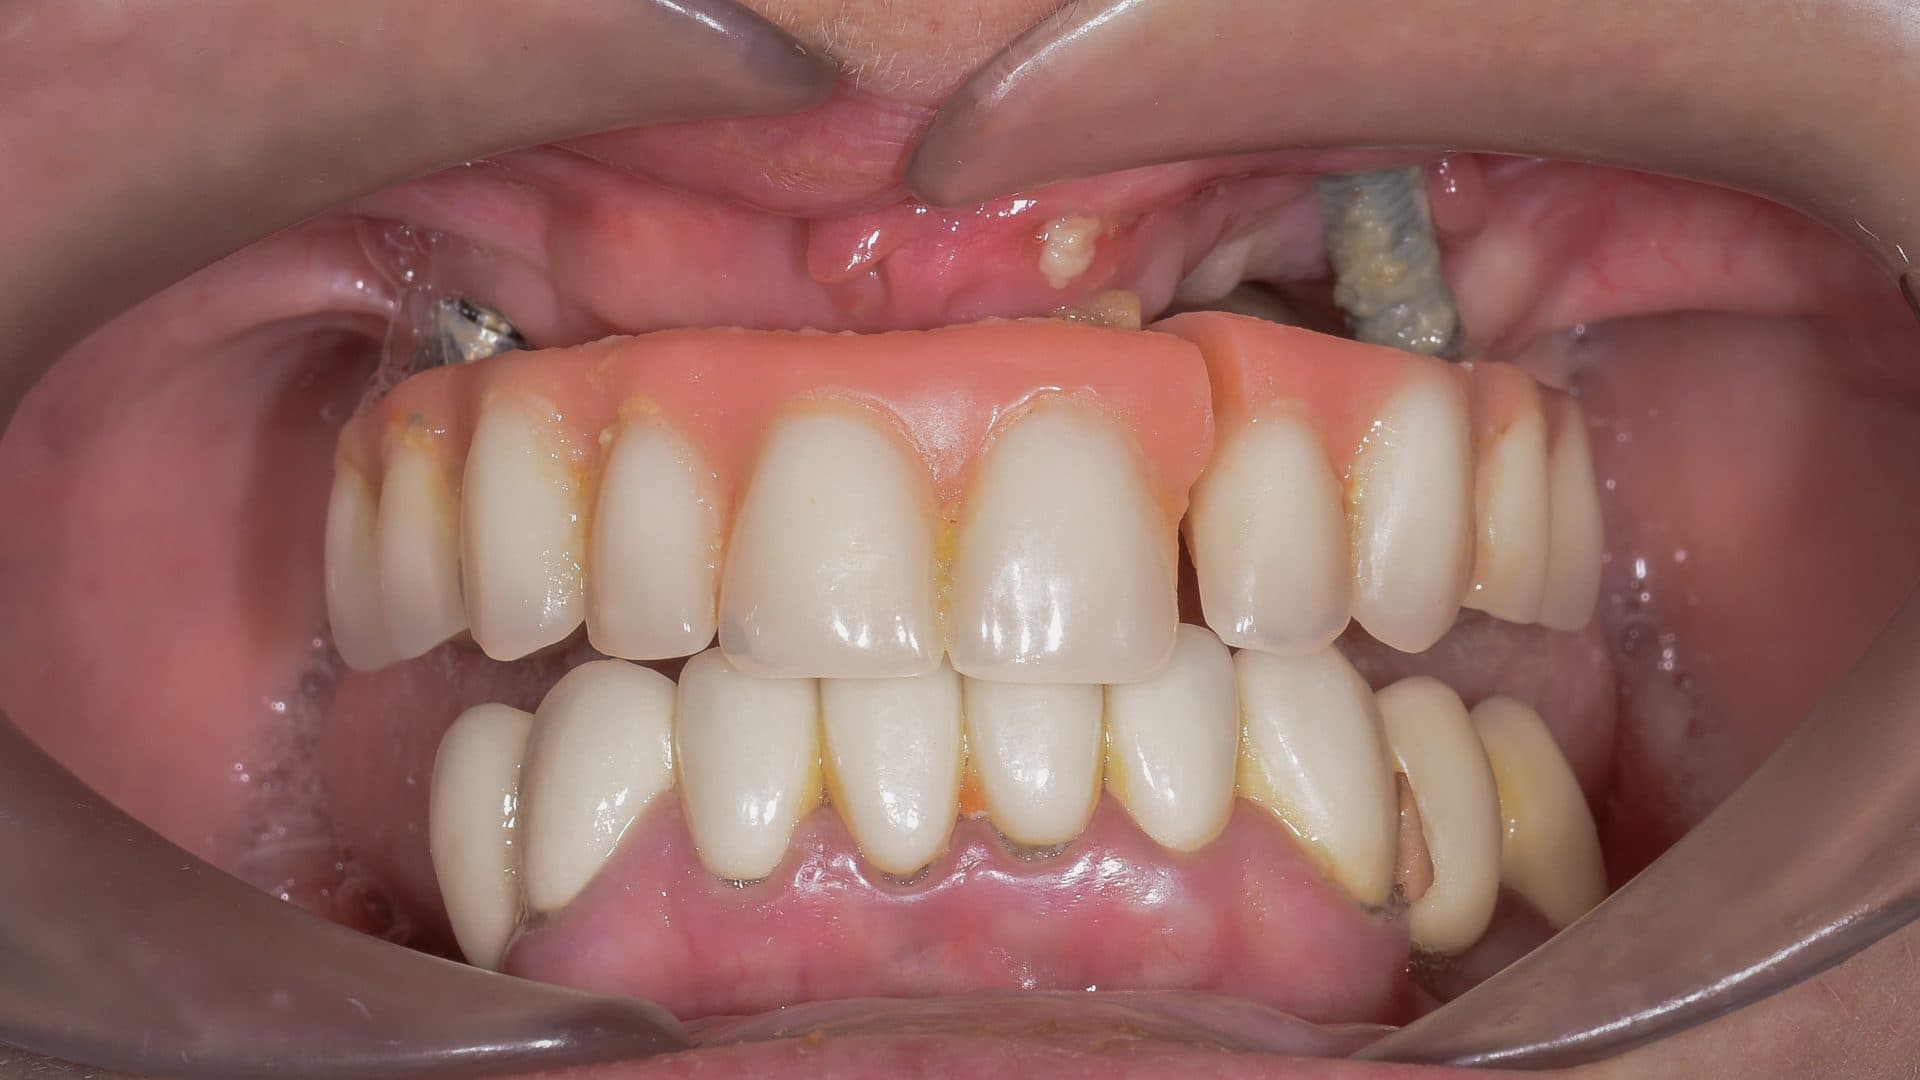

For suitable candidates, All-on-4 Plus® dental implants treatment can be transformative and offers an incredible solution for people who wear dentures, or those with deteriorated teeth and who want to avoid having to wear a plate, though in the wrong hands it can be quite the opposite.

Here is a graphical overview of the ideal situation compared to poor standards with All-on-4 Plus® dental implants.

Ideal Situation

Poor Standards